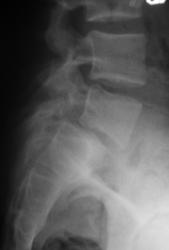

Молодой человек, занимаясь в спортзале, неаккуратно взял вес. Беспокоят боли в пояснице.

Истинный передний спондилолистез I степени и незаращение дужки L5

+1. Spina bifida S1.

На сколько я понимаю, при описании смещений в сегментах позвоночного столба принято оценивать смещение более краниального позвонка (как, например, при переломах оценивают смещение дистального отломка). С этой позиции, "Спондилолистез крестца кзади" звучит не совсем корректно.

На мой взгляд, сложно сказать явился ли листез следствием травмы (гипернагрузки), предыдущих снимков скорее всего нет. но исходя из умозаключения "где тонко, там и рвётся", смею предположить, что причина жалоб пациента находится именно на уровне спондилолистеза. ...правда, как облачить это в форму заключения протокола рентгенографического исследования я не знаю...

Если бы такой листез был следствием однократной гипернагрузки, думаю, что без инвалидной коляски бы не обошлось. Но о дальнейшем занятии таким спортом нужно задуматься.